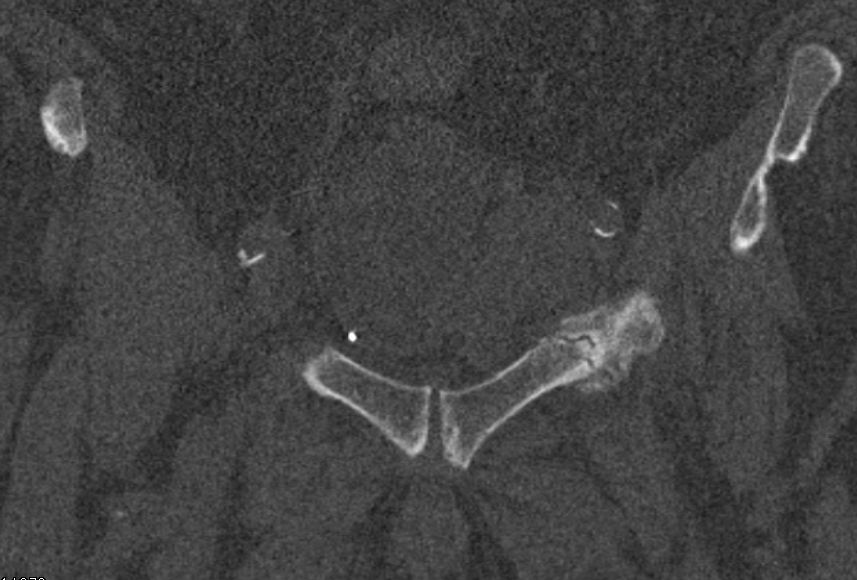

| Knochenmetastasen | 72-jähriger Patient, der vor 3 Jahren ein Harnblasen-Ca hatte: Blasenteilresektion. | Vor 2 Jahren 1. Rezidiv T1 G2: TUR-B. Vor einem Jahr 2. Rezidiv: Blasenteilresektion pT3a G3. | Vor 4 Monaten Lungenmetastastasen. Jetzt Schmerzen beim Sitzen und Belastung des linken Beins. |

Frische lytische Metastase im linken Sitzbein![]() |